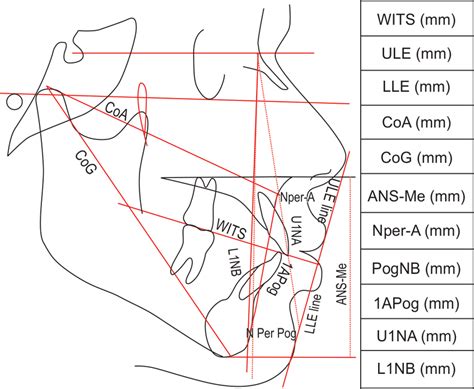

در این عکس، نقاط آناتومیک مشخصی توسط متخصص تعیین شده و بر اساس خطوط و زوایا تحلیل میشوند. این اطلاعات برای تشخیص دقیق و طراحی طرح درمان لازم است.

۲. علامتگذاری نقاط آناتومیک

نقاط خاصی روی عکس مشخص میشوند که مبنای اندازهگیری هستند.

۳. اندازهگیری زوایا و فواصل

زاویهها و خطوط مهمی مانند:

SNA

SNB

ANB

و شیب دندانهای بالا و پایین محاسبه میشود.